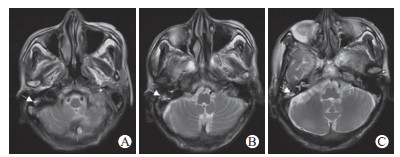

患者入院当天予以更昔洛韦(0.25 g静脉输注, 每12 h 1次)抗病毒、头孢曲松钠和奥硝唑经验性抗感染治疗,辅以控制癫痫、抗氧化、降压降糖、补钾补钠、营养支持等治疗。患者症状进一步加重。2022年9月24日,治疗前头颅MRI检查提示T2加权成像(T2-weighted imaging,T2WI)、液体衰减反转恢复(fluid-attenuated inversion recovery,FLAIR)、弥散加权成像(diffusion-weighted imaging,DWI)序列可见双侧额、颞叶及海马区异常信号(右侧为著)(图 1A~1H),FLAIR序列可见“刀切征”(图 2),磁敏感加权成像(susceptibility-weighted imaging,SWI)可见额叶、颞叶、枕叶及基底节区少量微出血灶(图 3);脑脊液外送检测结果回报:脑脊液HSV-Ⅰ型DNA检测阳性,血清HSV-Ⅰ型抗体IgG(+),巨细胞病毒、EB病毒、细菌及真菌二代测序检测均为阴性,综合分析后该患者HSE诊断明确。

图  3   患者治疗前头颅SWI检查

2022年9月24日,治疗前头颅SWI检查:A、B、C、D、E为SWI序列,白色箭头所指可见额叶、颞叶、枕叶及基底节区少量微出血灶.SWI:磁敏感加权成像.

HSE常合并其他病原体感染,若诊疗不当,病情会加重[20, 23]。本例患者合并有肺部感染,通过动态复查血液学感染指标、胸部CT,开展病原学检测和药敏试验,对抗感染药物从经验性使用调整为精准性使用,患者肺部感染预后良好。可见,在HSE诊疗期间,需动态监测感染指标变化,尽早完善病原体及药敏检测,及时准确干预。HSE可大大增加出血或血栓等疾病并发风险[24-26]。本例患者发病第10天出现促凝血相关指标升高,考虑HSE存在继发性血栓形成可能,予以达肝素钠抗凝治疗。另外,鉴于该患者凝血酶原比值及凝血酶原时间均有所增高,加用维生素K1预防凝血障碍导致的可能性出血。维持该治疗方案1周后复查,凝血指标接近正常水平。MRI-SWI序列可精确反映病毒性脑炎患者颅内病灶的出血量,对重度病毒性脑炎具有较高的预测价值[27-28]。本例患者头颅MRI-SWI序列可见额叶、颞叶、枕叶及基底节区少量微出血灶,提示病情较重。